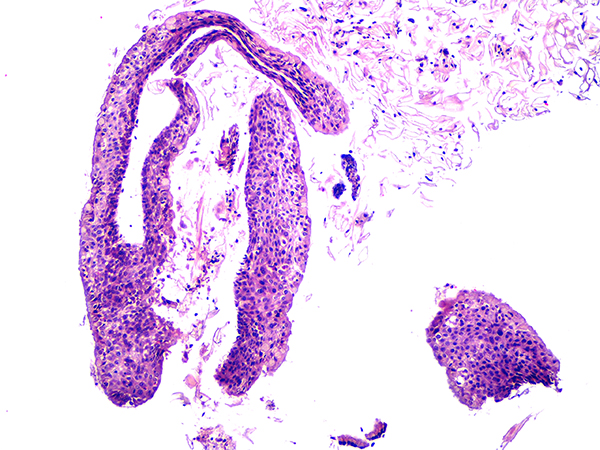

Case 3

Soft Bx CIN 2-3 10x - Low Power